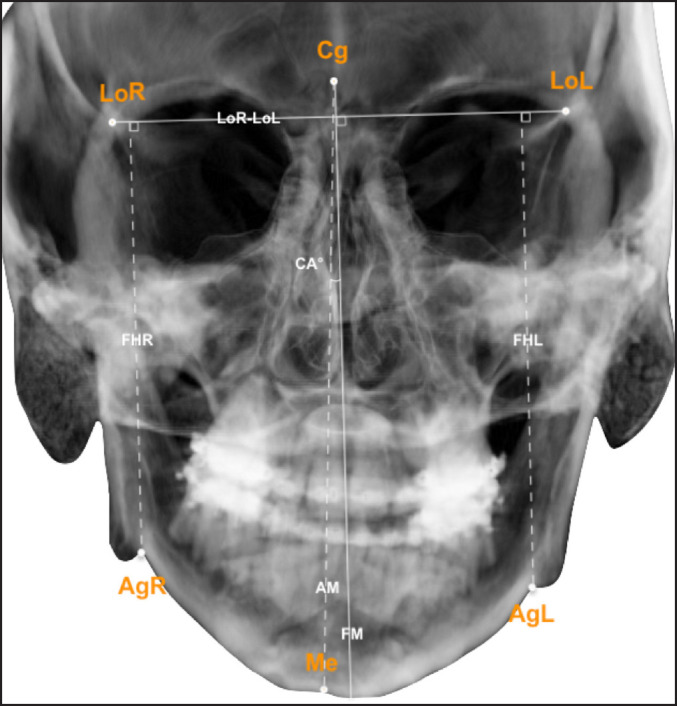

Material and methods: Nineteen patients with juvenile idiopathic arthritis of the temporomandibular joint (TMJ) and dentofacial deformities were included. All patients were treated with combinations of bilateral sagittal split osteotomy, Le Fort I and/or genioplasty, between September 10, 2007 and October 17, 2017. Analysis of patient symptoms and clinical registrations, and frontal/lateral cephalograms was performed pre- and postoperative and long-term (mean: 3.8 and 2.6 years, respectively).

Results: Patients experienced no changes in orofacial symptoms or TMJ function, and stable normalisation of horizontal and vertical incisal relations at long-term (horizontal overbite; vertical overbite: P < 0.05). Mandibular lengthening was achieved postoperatively (from mean 79.7 to 87.2 mm; P = 0.004) and was stable. Sella-nasion to A point (SNA) and sella-nasion to B point (SNB) angles increased postoperatively (SNA, mean 79.9° to 82.8°; P = 0.022 and SNB, mean 73.9° to 77.8°; P = 0.003), however, largely reverted to preoperative status at long-term.